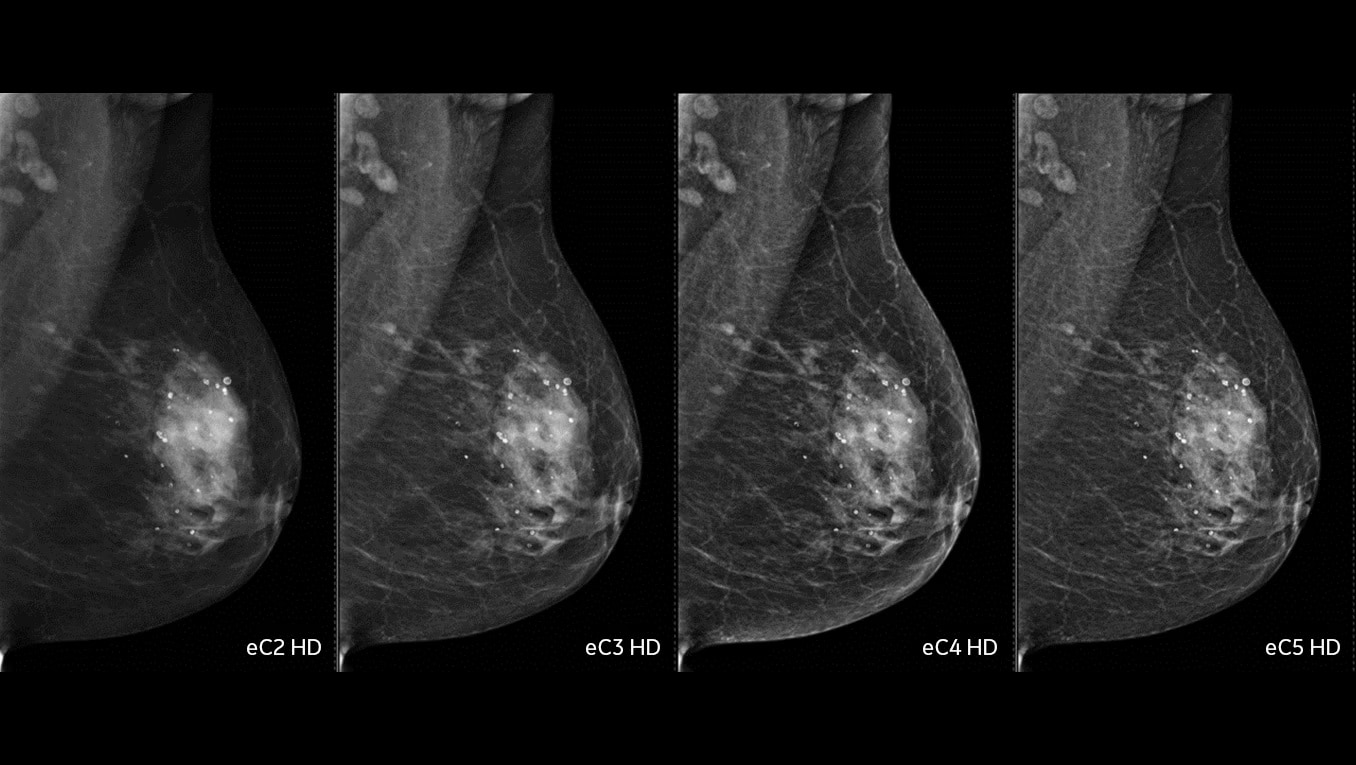

Lowest patient dose

Pristina mammography has the lowest patient dose of all FDA approved DBT systems3.